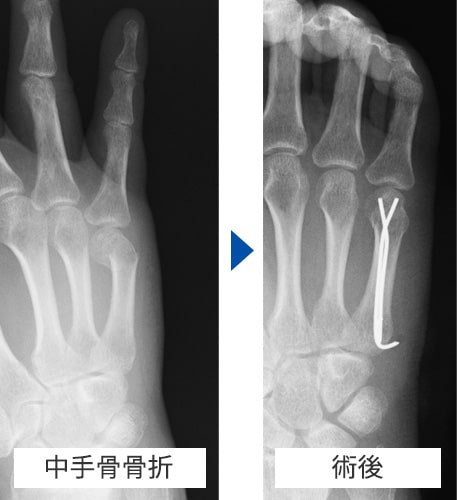

中手骨骨折 術前・術後写真

中手骨骨折術前・術後

原因

壁を殴ってしまったり、転倒した際に強打してしまったりして生じます。

症状

手や指が腫れて、痛くて動かせなくなります。変形を認める場合もあります。

治療方針

転位やズレの程度で治療方針を決めます。指の骨折の治療で重要なことは長期間固定をして拘縮を作らないことです。ほんの数週間の外固定により骨折部以外の関節も固くなってしまい、また少しの変形であっても指を握った時に重なったりする重篤な後遺症が生じることがありますので注意が必要です。手外科専門医にかかることをお勧めします。